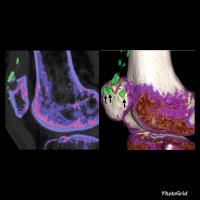

Although diagnosing gout generally is straightforward, atypical disease may present a challenge if it is associated with unusual symptoms or sites, discordant serum urate level, or mimics of gout. Dual-energy computed tomography (CT) may be used to differentiate urate crystals from calcium by using specific attenuation characteristics, which may help diagnose gout. In patients with known tophaceous gout, dual-energy CT may be used for serial volumetric quantification of subclinical tophi to evaluate response to treatment.

Dual-energy CT can quantitatively identify monosodium urate crystal deposits with high sensitivity and specificity within joints, tendons, and periarticular soft tissues.

Given the utility of dual-energy CT in challenging cases and its ability to provide an objective outcomes measure in patients with tophaceous gout, dual-energy CT promises to be a unique and clinically relevant modality in the diagnosis and management of gout.